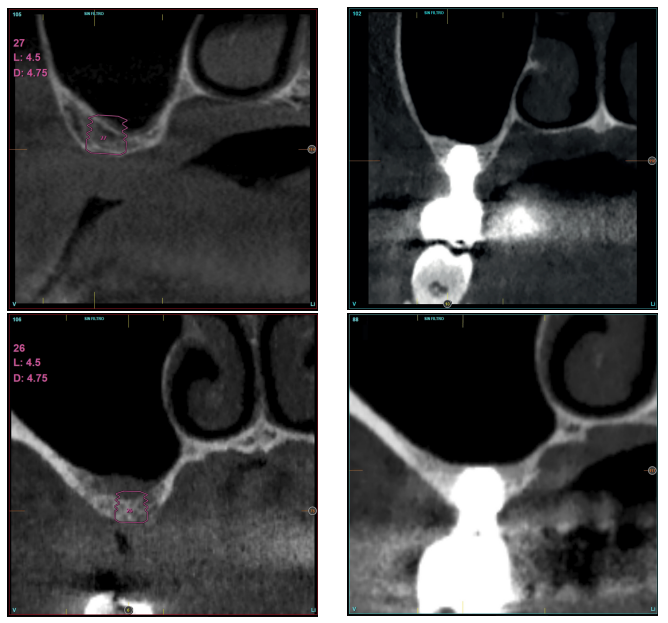

Todos los implantes fueron rehabilitados en dos fases y todos ellos fueron ferulizados a otros implantes en la rehabilitación. En todos los casos se realizó prótesis atornillada de más de un implante con elementos intermedios (transepiteliales), ferulizándose a otros implantes de longitud de 4,5 o 5,5 mm. En todas las situaciones se realizó una prótesis de carga progresiva a los 6 meses de la inserción del implante consistente en una estructura provisional terminada en resina para pasar a una prótesis definitiva metalcerámica. En todos los casos se conservan los transepiteliales iniciales para mantener el hermetismo logrado en la primera fase de la confección de la prótesis.

En las Figuras 2- 19 se muestra uno de los casos incluidos en el estudio.

la oseointegración del implante 6 meses después de la cirugía. Se observa una ganancia ósea de 4 mm.

implante y el volumen óseo ganado y conservado tras la función de los implantes.